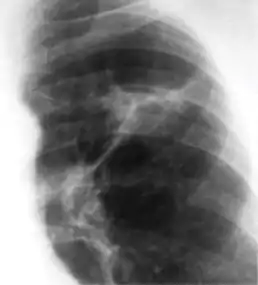

2. Any cavitary lesion - Lucency (darkened area) within the lung parenchyma, with or without irregular margins that might be surrounded by an area of airspace consolidation or infiltrates, or by nodular or fibrotic (reticular) densities, or both. The walls surrounding the lucent area can be thick or thin. Calcification can exist around a cavity.

Chest X-ray of a person with advanced tuberculosis: Infection in both lungs is marked by white arrow-heads, and the formation of a cavity is marked by black arrows.